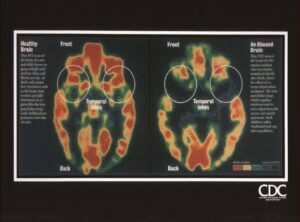

Brain_Abuse_ComparisonBy Matt Perelstein / October 19, 2025 Download File Type: jpg Categories: LeftBrain_RightBrain Author: Matt Perelstein